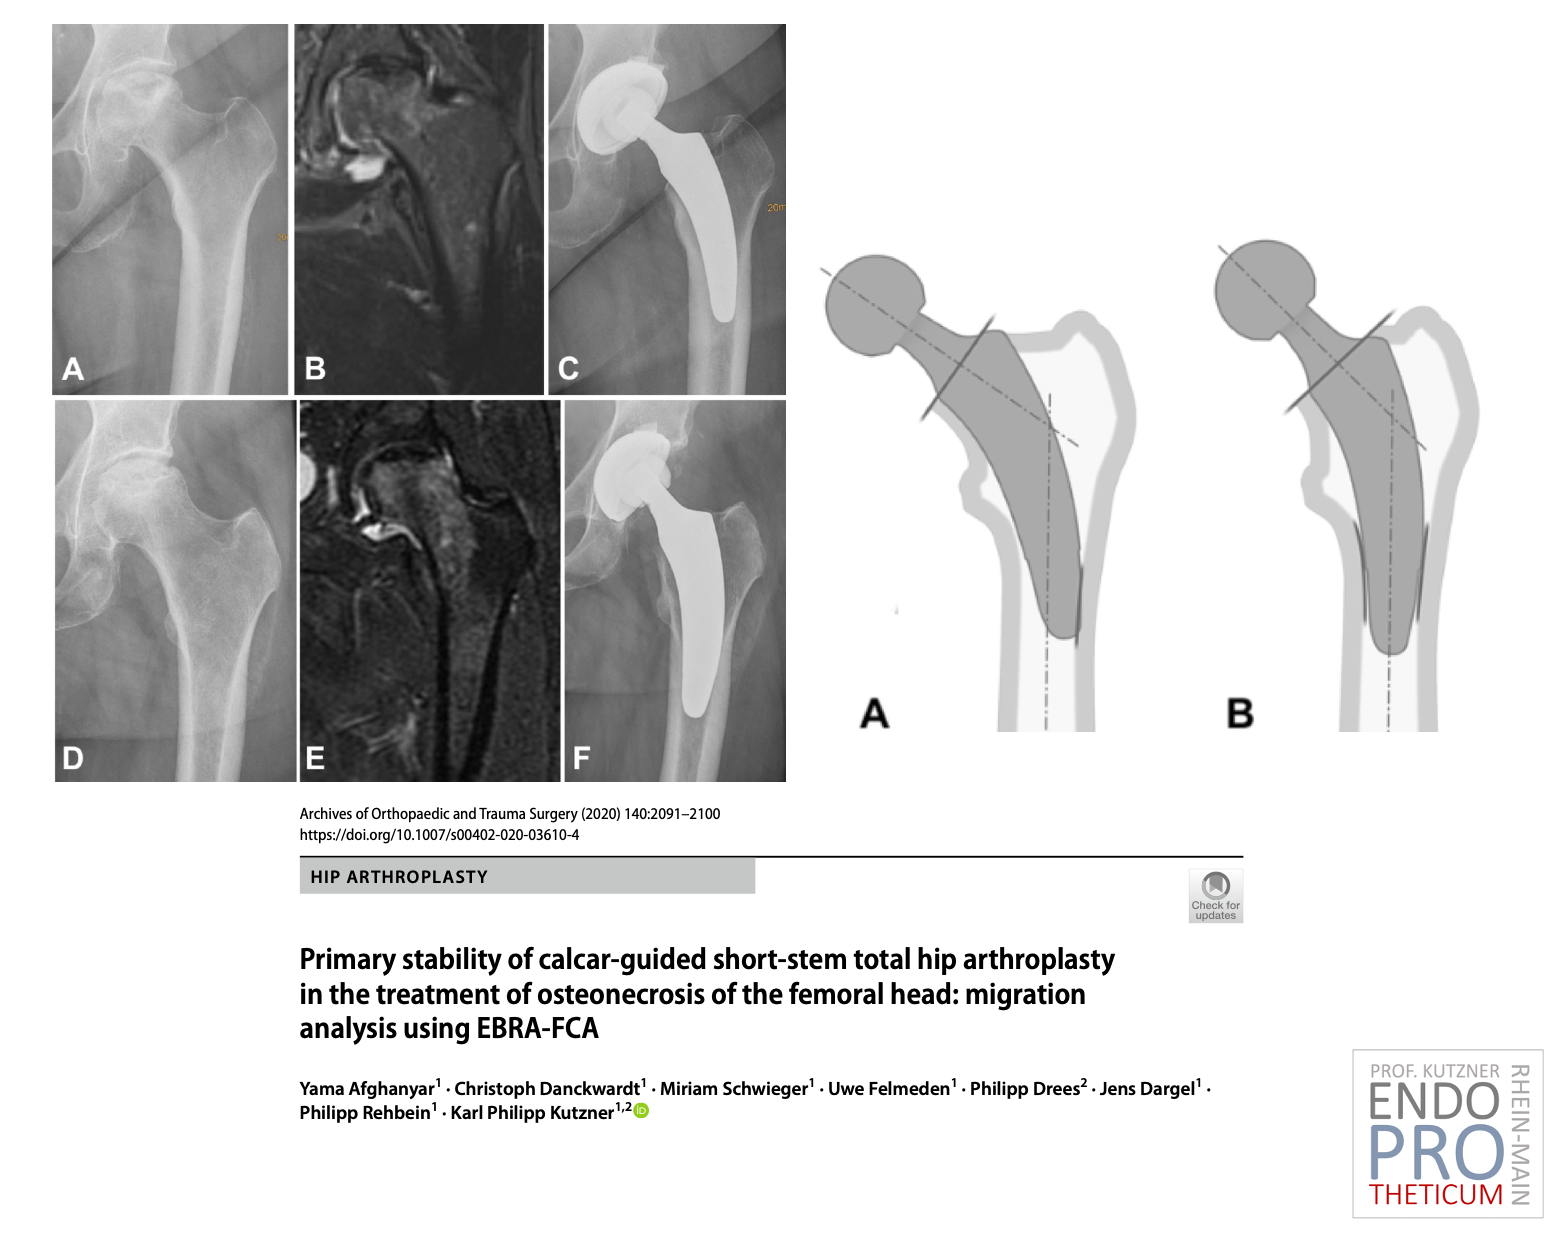

El concepto de vástagos cortos modernos guiados por calcar en la artroplastia de cadera tiene como objetivo la reconstrucción precisa de la geometría anatómica individual de la cadera. Se utiliza una técnica de implantación respetuosa con los huesos y los tejidos blandos junto con una carga fisiológica en la parte del fémur cercana a la articulación para preservar el hueso a largo plazo.

Los ejes cortos y redondos encajan perfectamente con ALMIS ACCESS mínimamente invasivo, no es necesario dañar los músculos; A diferencia de los ejes rectos convencionales, la implantación se logra mediante la técnica de "la vuelta de la esquina".